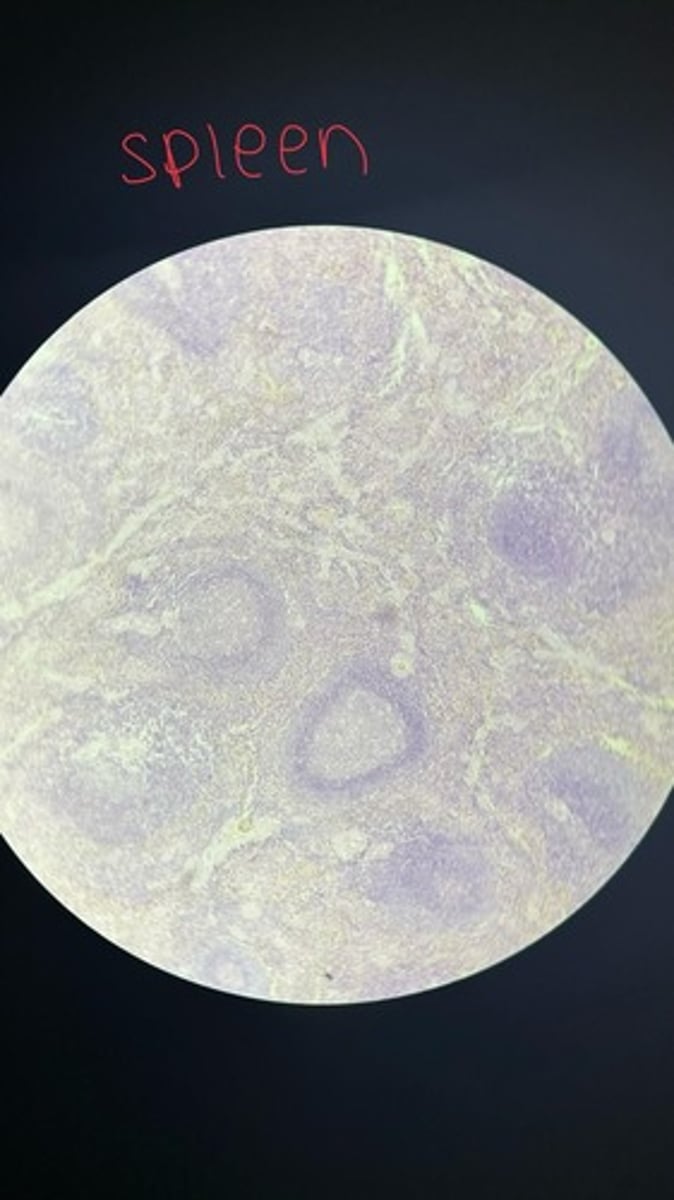

Spleen HE

Spleen HE

Spleen HE